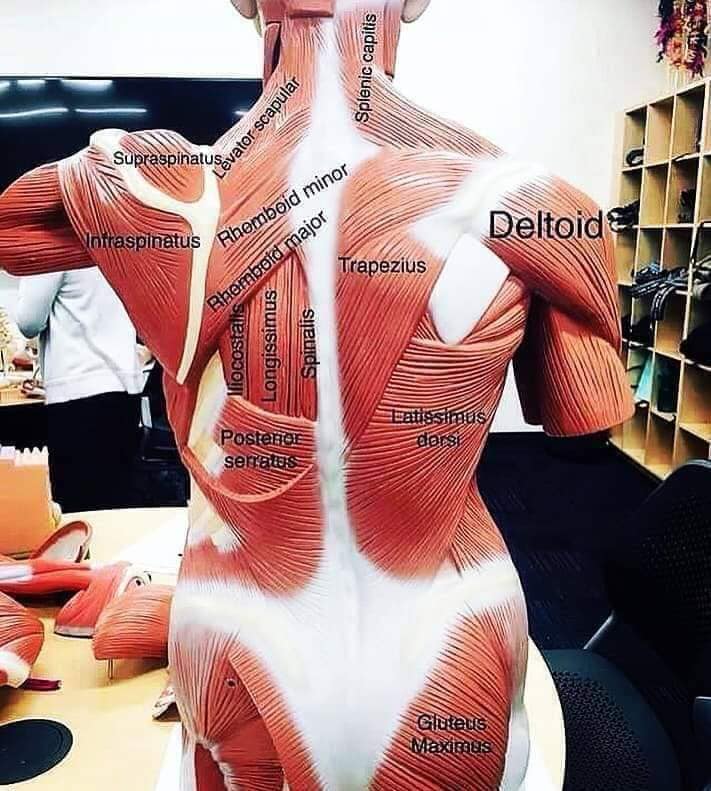

Спинні м'язи

Спинні м'язи виконують функції підтримки хребта, а також дозволяють здійснювати рухи тулуба.

Поверхневі спинні м'язи

М'язи, що піднімають лопатку: Трапецієподібний м'яз: великий м'яз, що покриває верхню частину спини. Його функція - підтримка і рух лопаток, а також забезпечення стабільності хребта.

М'язи, що ведуть лопатку до хребта: Широкий м'яз спини: великий м'яз, що розташований в нижній частині спини. Він відповідає за рухи плечей і лопаток, а також за розширення верхньої частини тулуба.

Глибинні спинні м'язи

М'язи, що забезпечують стабільність хребта: М'язи, що розташовані між хребцями: включають мускулатуру, яка забезпечує стабільність і підтримку хребта, а також дозволяє здійснювати рухи хребта.

М'язи, що здійснюють ротацію та нахили

М'язи, що забезпечують ротацію хребта: Ротаційні м'язи: допомагають у здійсненні обертальних рухів тулуба, а також у підтримці рівноваги і стабільності хребта.